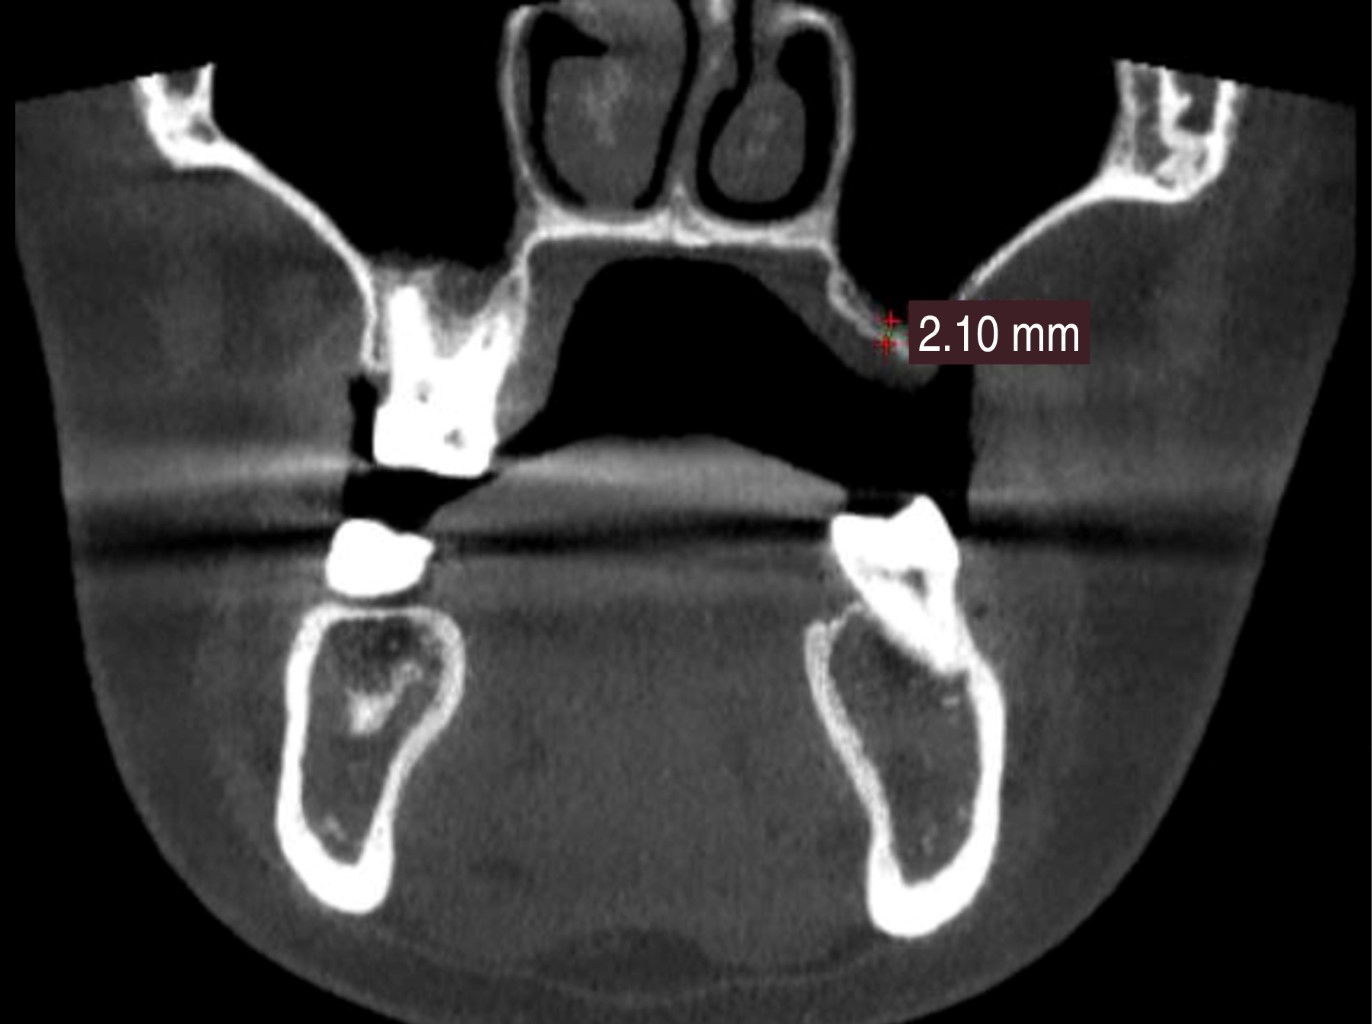

Introduction: the invention of computed tomography and the development of interactive software to allow digital planning has drastically improved the accuracy of procedures in oral surgery, especially in the planning of dental implants. In the posterior maxilla, due to the presence of the maxillary sinus, the height of the residual bone less than 3 mm is a critical factor that can affect the stability and survival of the implant. Digital planning facilitates and shortens surgical times, in addition to providing safety for accurate sinus elevation and subsequent implant placement by making a surgical guide. Objective: to describe the effectiveness of digital planning in predicting and recording bone height gain through maxillary sinus elevation and subsequent guided surgery for implant placement. Case report: a clinical case is presented in which, by means of digital planning, a maxillary sinus elevation technique is performed by lateral approach and subsequent implant placement by implementing a surgical guide. Conclusion: despite the numerous advantages of digital planning for sinus elevation and surgical guide design, there is a gap in the literature for standardized protocols for this purpose. Our digital planning protocol for sinus elevation and surgical guide design for implants is effective, accurate and predictable.

Figure 1

Figure 2

Figure 3

Figure 4

Figure 5

Figure 6

Figure 7

Figure 8

Figure 9